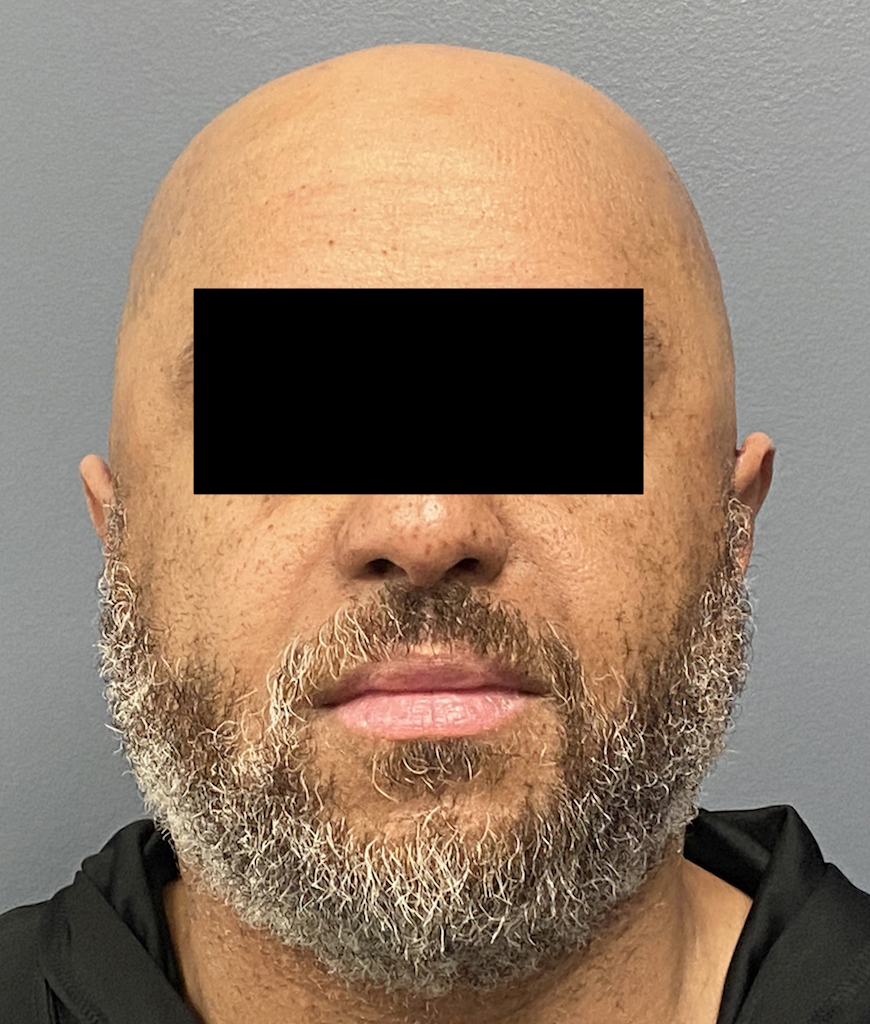

Patient 100

Desire for reshaping of an asymmetric flat back of the head in a shaved head male.

A combined back of the head reshaping procedure was done with a custom skull implant, sagittal ridge reduction and a right temporal muscle reduction.

Desire for reshaping of an asymmetric flat back of the head in a shaved head male.

A combined back of the head reshaping procedure was done with a custom skull implant, sagittal ridge reduction and a right temporal muscle reduction.